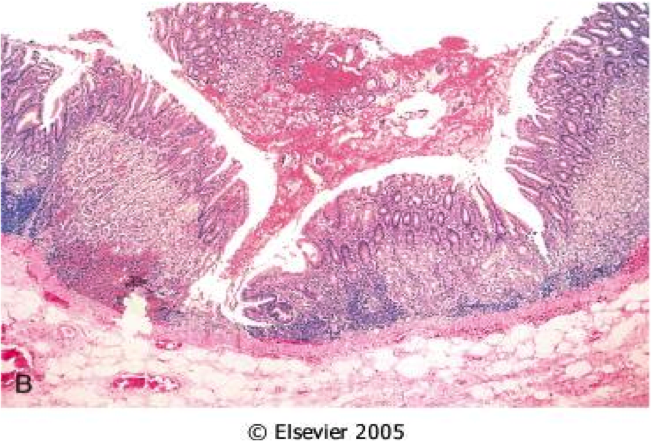

normal gastroesophageal junction

stratified sqaumous of esophagus

simple columnar of gastric cardia

GERD

GERD on bottom

squamous proliferation, papillae elongation, basal cell hyperplasia, inc. inflammation in lamina propria, decreased surface maturation

Note: biopsy findings are not specific! cannot make diagnosis w/ biopsy alone must have clinical info as well

Barrett’s esophagus

Endoscopically recognizable columnar metaplasia of the esophageal mucosa that is confirmed pathologically to have intestinal metaplasia, the latter defined by goblet cells

Both the endoscopic and pathologic components should be present to establish BE.

Barrett’s esophagus: columnar metaplasia (intestinal metaplasia)+goblet cells